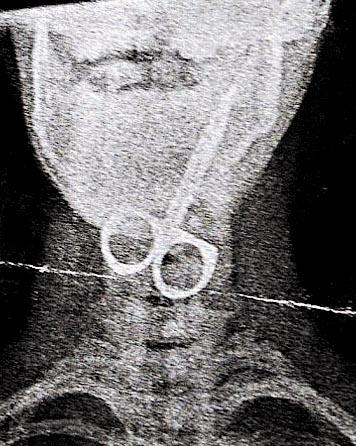

有學習障礙的弗朗西斯,不懂說話,更不知危險為何物。今年8月,他竟把剪刀放入口,骨嘟吞下。媽媽之後見兒子發出驚恐的聲音兼咳血,立即把兒子送院,X光照出他喉間卡了一把剪刀(圖二)。

幸好弗朗西斯只受輕傷,手術順利,他現已康復。媽媽說:「那是我一輩子最糟的一天。我沒想過剪刀吞得下肚,所以我真的嚇呆了。」

(圖二)